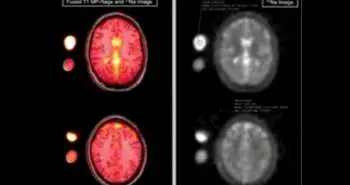

In 26 patients (24 women) with migraine who underwent diffusion tensor imaging afterwards using a 1.5-tesla magnetic resonance scanner, radioimmunoassay was used to evaluate the interictal plasma PACAP38-LI.  Tract-based spatial statistics present in the FMRIB's Software Library was used to analyze data.

Interictal plasma PACAP38-LI showed considerable relation with mean diffusivity (p < 0.0179), primarily in the bilateral occipital white matter scattering into the temporal and parietal white matter.  A positive link between interictal PACAP38-LI in the left optic radiation, and left posterior corpus callosum and axial, and radial diffusivity was observed. There was no considerable relationship noted between PACAP38-LI and fractional anisotropy. The disease duration was considered as nuisance regressor in the model. Association of PACAP38-LI with mean and axial diffusivity in the left thalamus was observed.